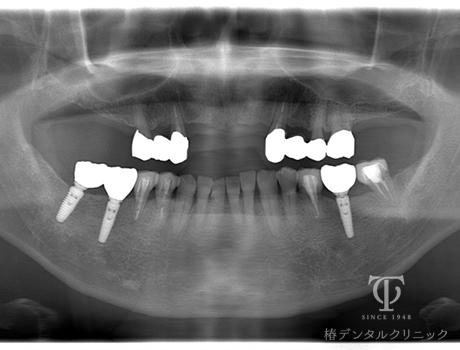

インプラント治療後レントゲン

-

- 症状

- 右上の痛み

- 治療期間

- 約1年半

- 治療費用

- (上顎)インプラント治療:473,000円×2

(上顎)AGCテレスコープ義歯:1,500,000円

(下顎)インプラント治療:473,000円×2

右上の歯が痛いということで来院されました。インプラントとAGCテレスコープという方法でかみ合わせを再構築しました。